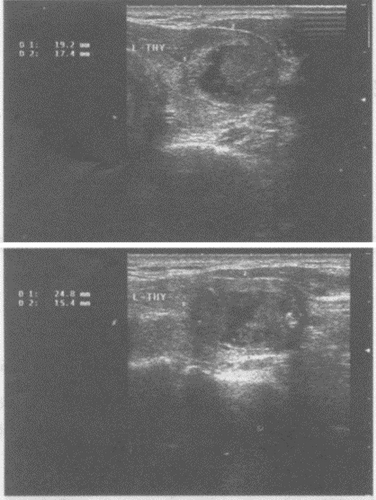

34、单项选择题

患者颈部肿大,可扪及肿块。如图,提示为()。

A.甲状腺腺瘤

B.结节性状腺肿大

C.甲状腺癌

D.甲状腺炎症

E.甲状腺囊肿